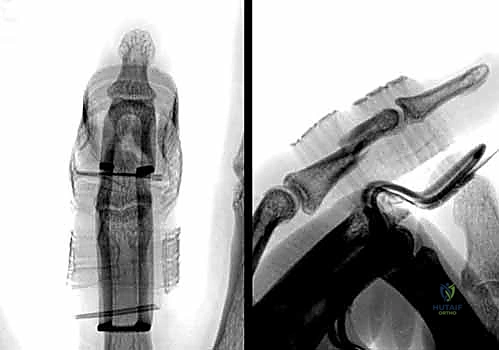

1. الرد المغلق والتثبيت بأسلاك كيرشنر (CRPP - Closed Reduction and Percutaneous Pinning):

تُعد هذه الطريقة الأقل توغلاً. يقوم الدكتور هطيف برد الكسر يدوياً تحت توجيه جهاز الأشعة السينية المباشر (C-arm) في غرفة العمليات، ثم يقوم بإدخال أسلاك معدنية دقيقة (K-wires) عبر الجلد لتثبيت العظم.

* المزايا: لا تتطلب شقاً جراحياً كبيراً، تحافظ على الإمداد الدموي للعظم، وتقلل من خطر التصاقات الأوتار.

* العيوب: تتطلب إبقاء جزء من السلك خارج الجلد (عادةً)، مما يستلزم إزالتها في العيادة بعد 4-6 أسابيع.

2. الرد المفتوح والتثبيت الداخلي (ORIF - Open Reduction and Internal Fixation):

في الكسور المفتتة أو المعقدة، يقوم الدكتور هطيف بعمل شق جراحي دقيق (غالباً من الجانب لتجنب الأوتار الظهرية) لكشف الكسر وإعادة ترتيب الشظايا العظمية بدقة متناهية، ثم تثبيتها باستخدام:

* البراغي الساحبة (Lag Screws): تُستخدم في الكسور المائلة الطويلة أو الحلزونية لتوفير ضغط قوي بين حواف الكسر.

* الصفائح والبراغي الدقيقة (Mini-plates and Screws): تُستخدم في الكسور العرضية أو المفتتة لتوفير تثبيت صلب وقوي يسمح بحركة الإصبع في اليوم التالي للعملية.